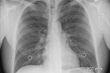

Czołowy polski specjalista w zakresie kardiologii interwencyjnej przyjechał do Łomży, by pomóc przeprowadzić zabiegi angioplastyki. Dzięki jego pomocy, wszyscy pacjenci czują się już dobrze i zostali już wypisani do domów.